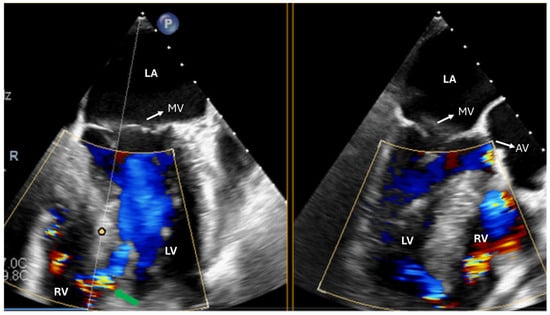

| TV repair | Describe TR mechanism Describe TV anatomy Measure TV annulus | Exclude iatrogenic TV stenosis |